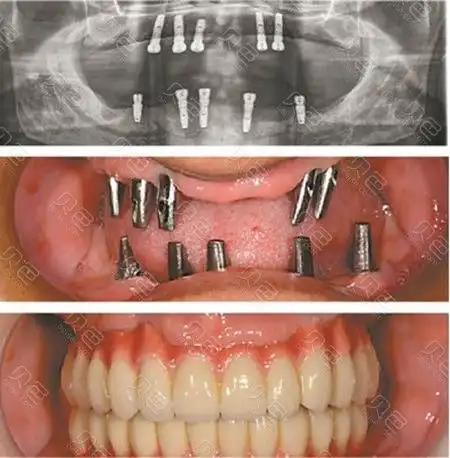

「保姆级攻略」想做种植牙:一篇文章教你找到最靠谱的种植方案!

教你如何正确选择种植牙!